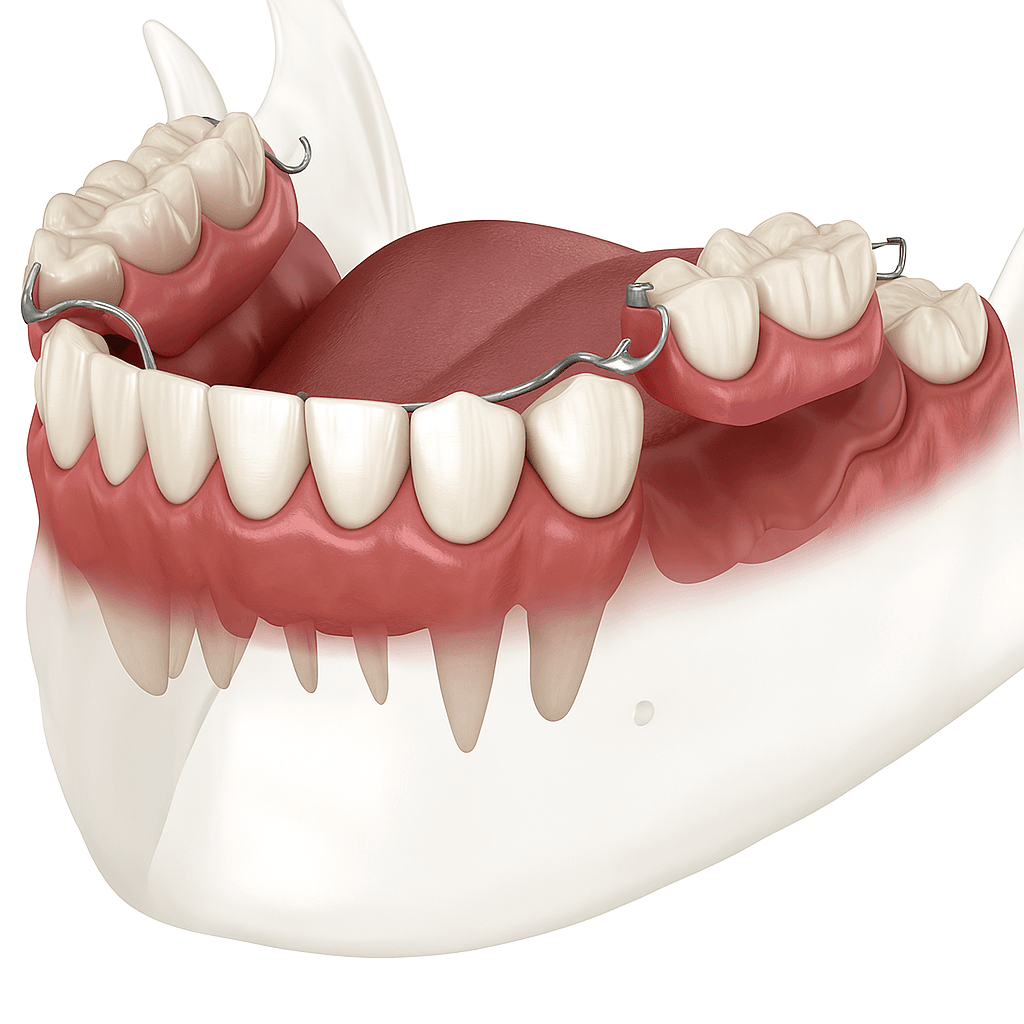

- • Implanty można dostosować do różnych sytuacji klinicznych od pojedynczych braków zębowych po pełną rekonstrukcję łuków zębowych.